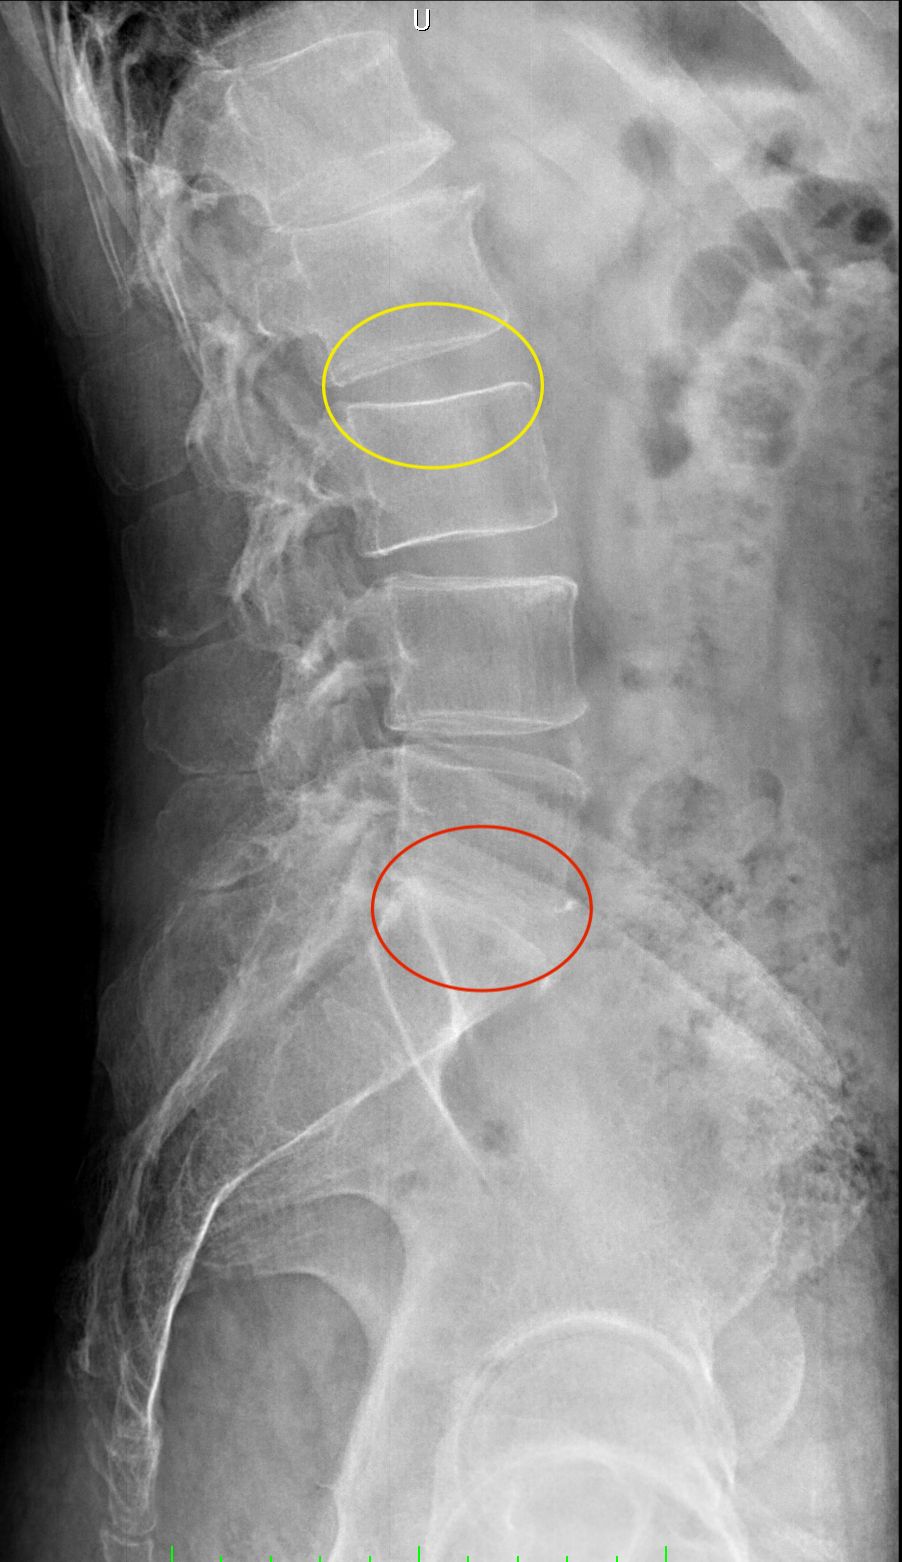

Dopo la laurea e la specializzazione in Neurochirurgia con lode presso il Policlinico Agostino Gemelli, ho dedicato la mia formazione esclusivamente alla cura delle malattie della colonna vertebrale e del midollo spinale, come ernie del disco, stenosi del canale vertebrale, spondilolistesi, metastasi vertebrali e tumori del midollo spinale, attraverso esperienze presso centri di riferimento italiani ed internazionali e a numerosi corsi e master di II livello.

Queste patologie si manifestano con sintomi neurologici (ad esempio: dolore o perdita di forza ad un arto, formicolii, rigidità o perdita di coordinazione alle mani o durante la marcia) oppure con sintomi meccanici (ad esempio: mal di schiena prevalente durante il movimento). Una valutazione specialistica deve mirare a correlare i sintomi clinici con le alterazioni presenti alle immagini radiologiche, ed a guidare il paziente attraverso il percorso di cura, finalizzato al recupero della sua ottimale qualità di vita.

• ernia del disco cervicale, toracica e lombare;

• stenosi del canale vertebrale cervicale e lombare;

• spondilolistesi cervicale e lombare;

• scoliosi degenerativa dell’adulto;

• cifosi degenerativa dell'adulto;

• deformità degenerative dell'adulto.